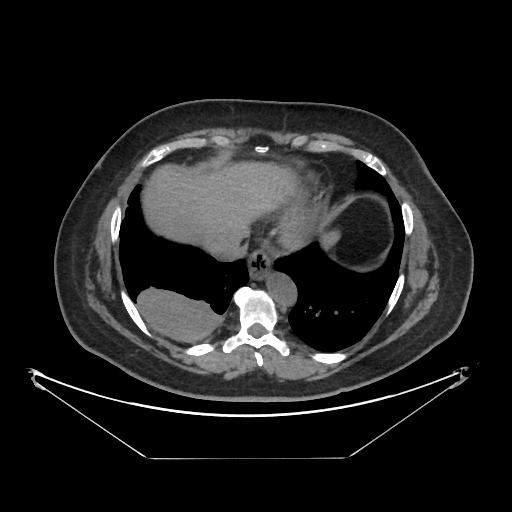

Original VENOUS CT scan

No window - Raw intensity values

Original VENOUS CT scan

Lung window (WL -600, WW 1500 → Low −1350, High +150)

Original VENOUS CT scan

Mediastinum window (WL 40, WW 400 → Low −160, High +240)

Image Grid

4×3 grid: Rows show different image types (Original NATIVE, Reconstructed NATIVE, Original VENOUS, Generated VENOUS), Columns show windowing techniques (No Window, Lung Window, Mediastinum Window)